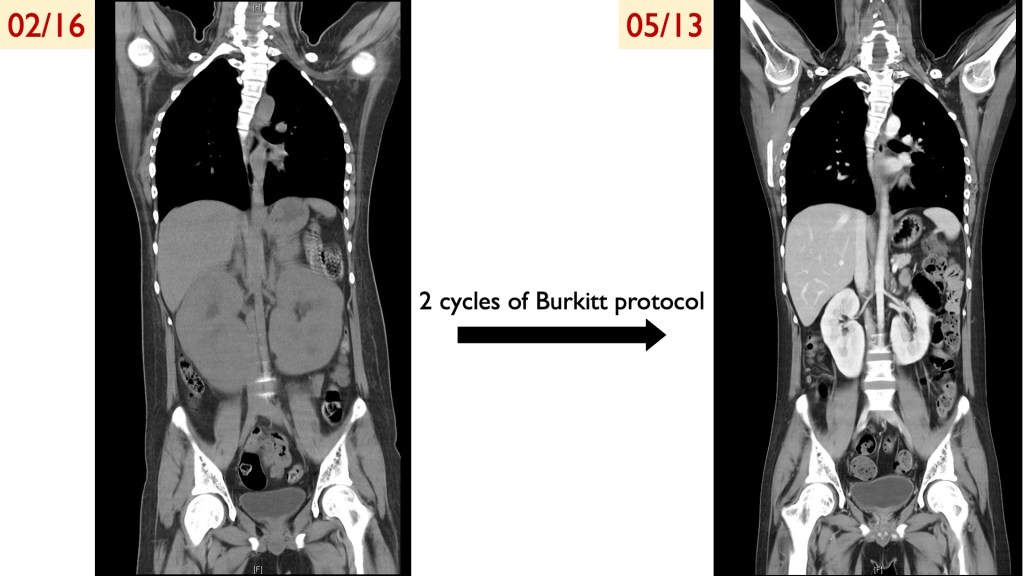

這次報告了一位新診斷的Burkitt lymphoma的病人。這位病人來到急診就呈現AKI + Tumor lysis syndrome+bilateral large kidney,但他underlying disease並沒有cancer,因此我們必須找出他的腫瘤。另外住院期間,他還發生了sepsis、respiratory failure、conscious change等等的問題。以上這些問題都隨著我們診斷了腫瘤,並積極治療之下(從在加護病房就給予intensive chemotherapy),整體病況迅速改善,順利拔管轉出加護病房。

Burkitt lymphoma是進展極快的惡性腫瘤,(有多快呢?張醫師提到有一位病人一週前來門診摸到拇指大小的腫塊,短短一週內進展成拳頭大。)但我們的病人在各個團隊努力下,治療效果極佳,目前疾病處於complete response。